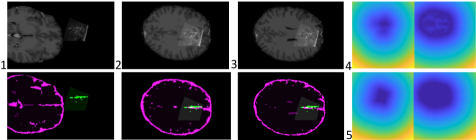

Refer to caption

Figure 3: Robustness test for decreasing overlap percentage. These barplots show the fraction of experiments that fall into each quality measure category (yaxis𝑦𝑎𝑥𝑖𝑠y-axis) considering the percentage of overlap (xaxis𝑥𝑎𝑥𝑖𝑠x-axis) for image overlap (left) and target area overlap right image (right).